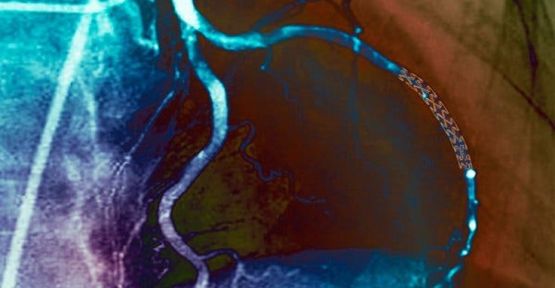

Yeni çalışma, yalnızca ilaç tedavisi gören hastaların daha fazla kalp krizi geçirmediğini veya ölüm oranlarının bypass ameliyatı geçiren ya da stent -daralmış arterleri açmak için küçük tel örgüler- takılanlardan daha sık olmadığını ortaya koydu.

Bu bulgunun ciddi biçimde tıkalı birkaç koroner arteri olan hastalar için geçerli olduğu görüldü. Bununla birlikte, stentleme ve bypass operasyonları, ‘anjina’* adı verilen inatçı göğüs ağrısından musdarip olan bazı hastalara da yardımcı oldu.

Hastalar, rastgele biçimde, yalnızca tıbbi tedavi ya da bir müdahale ve tıbbi tedavi almak üzere görevlendirildiler. Müdahale gören gruptakilerin dörtte üçüne stent takıldı; diğerlerineys e bypass ameliyatı yapıldı.

Dr. Maron’un aktardığı kadarıyla, bir egzersiz stres testi bir daralmayı ortaya çıkardığında, çoğu doktor tıkanıklıkları aramak için hastayı bir ‘kardiyak kateterizasyon’ laboratuvarına gönderir. Eğer bir tıkanıklık söz konusuysa, olağan uygulama bunu bir stent vasıtasıyla açmaktır. Şayet stent kullanımı -örneğin hastanın arterlerinin yapısı nedeniyle- mümkün değilse, bypass cerrahisi genellikle bir sonraki adım olur.